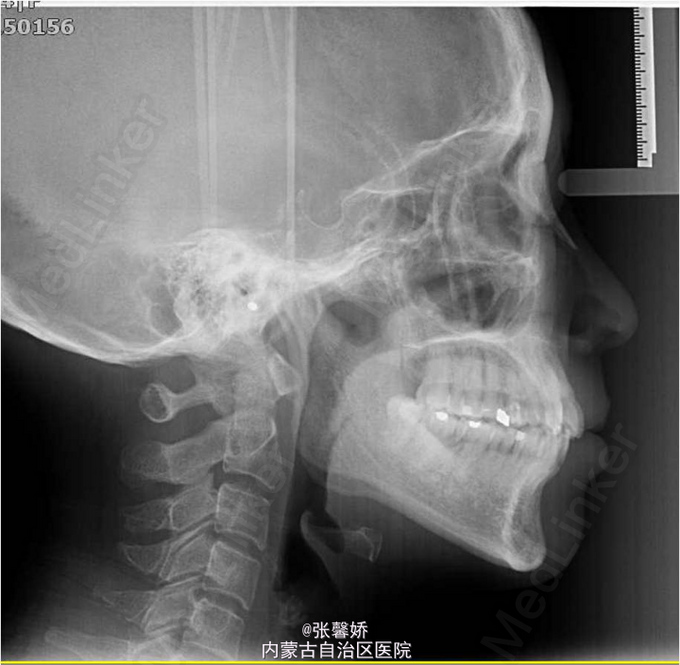

牙列中度拥挤;A2、D4反合 处理:时代天使隐形矫治器矫治 拔除C8、D8 适当下前牙邻面去釉 排齐整平上下牙列,改正A2、D4反合 治疗时间2年左右,矫治后牙齿排列整齐,咬合关系良好,患者满意。

一年后随访,患者咬合关系仍稳定,尖窝锁结良好。 隐形矫治适应证的选择很重要,适合中低难度的成人病例,患者的配合和依从性要求较高。 此患者术前全景片可见多个充填物,为龋易感患者,而且牙周也不是很好,隐形矫治没有拖槽更利于患者口腔卫生的维护,防止龋病的发生和牙周病的加重。